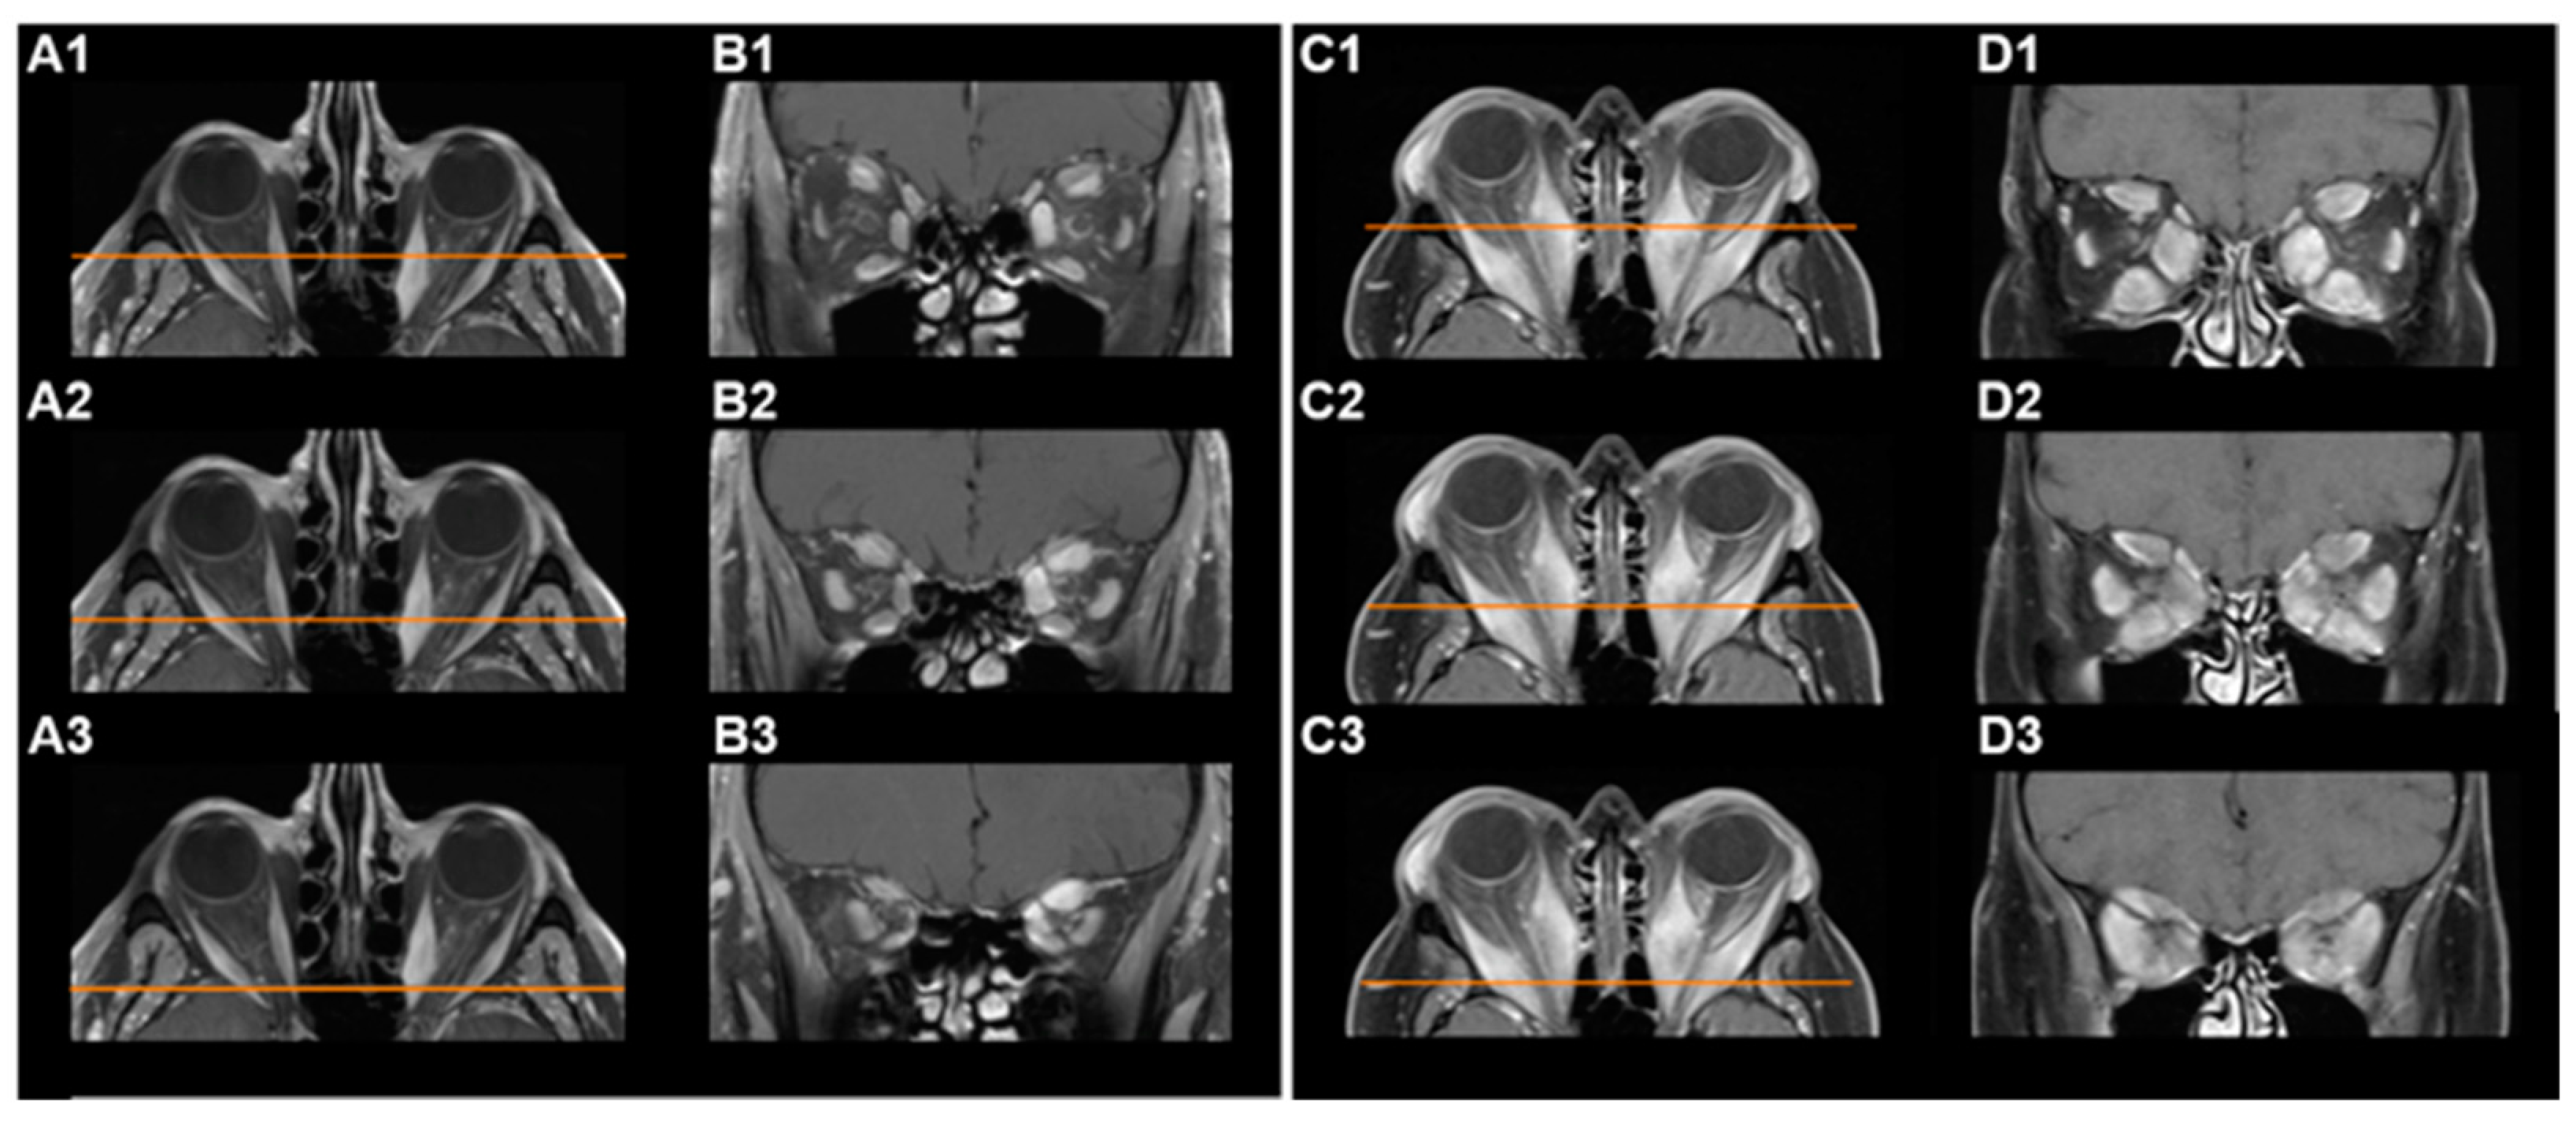

2.2. Volumetric Analysis